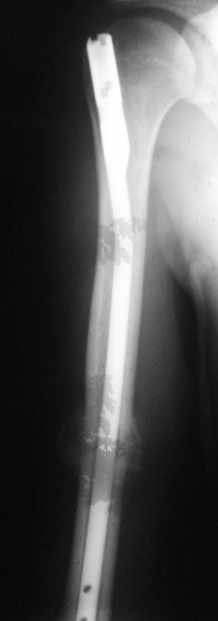

Блокируемый незаблокированный штифт.

Ортопедия и травматология Отправлено Andrey Sereda 29 Июнь 2008, 23:44

Уважаемые коллеги!Обратился пациент, оперирован не у нас.

однозначно не блокировать и не убирать - есть прекрасная мозоль и все отлично срастается. Мне плохо видно - выступает ли гвоздь проксимально ( кажется, нет, гвоздь строго в уровень с костью)?

Большая мозоль - здоровый организм УСПЕШНО компенсирует недостатки фиксации.

Раз есть боль в области плеча - скорее всего, таки травмируется ротаторная манжета плеча гвоздем - либо подождать еще месяцок и гвоздь убрать, пока он больному не разорвал манжету "в клочья", либо (в идеале, если есть желание, операционное время, инструмент того же производителя, которым пользовались в Склифе, понимание со стороны больного и т.д) - забить гвоздь на полсантиметра глубже и заблокировать одним проксимальным шурупом, чтоб предотвратить его миграцию в канале

Само же состояние перелома мне не внушает никаких сомнений или опасений

Гвоздь для плеча - дело не очень хорошее, и, честно говоря, на этих снимках показаний к такому методу лечения я никаких не вижу. Больше процент несращений, часто (до 20-30 процентов) встречаются осложнения со стороны плечевого сустава... Однако, это уже выходит за пределы обсуждаемой темы

Обычное дело, пусть разрабатывает давно, лучше с методистом. Тут по снимкам проблем не видно. Винты вводить необязательно - если хирург знает, что делает. Например, если получился хороший press-fit из-за несоответствия формы гвоздя и канала.